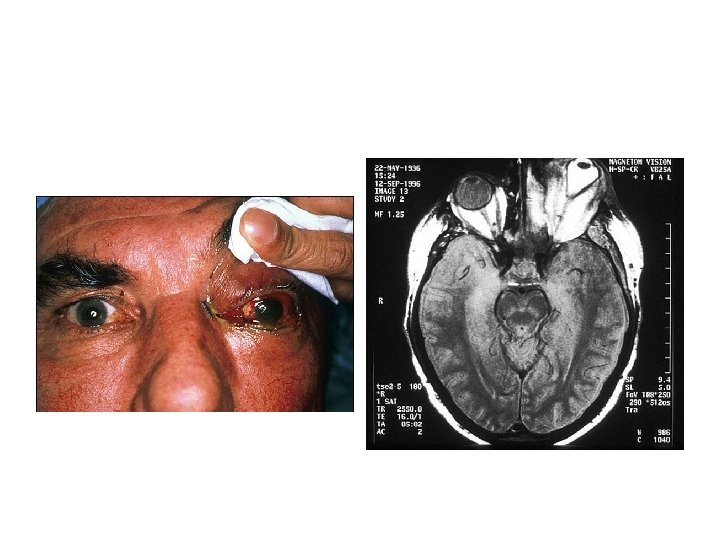

Autres infections • Cardio-vasculaires • Neuro-méningées • Autres : – Endophtalmies – Stomatologiques –…

Expression clinique • L’affection est strictement liée au SNC • présence de lésions herpétiques orales ou faciales rarement constatée (moins de 10%) n’a pas de valeur particulière. . • Aucun signe pathognomonique, examens complémentaires nécessaires.